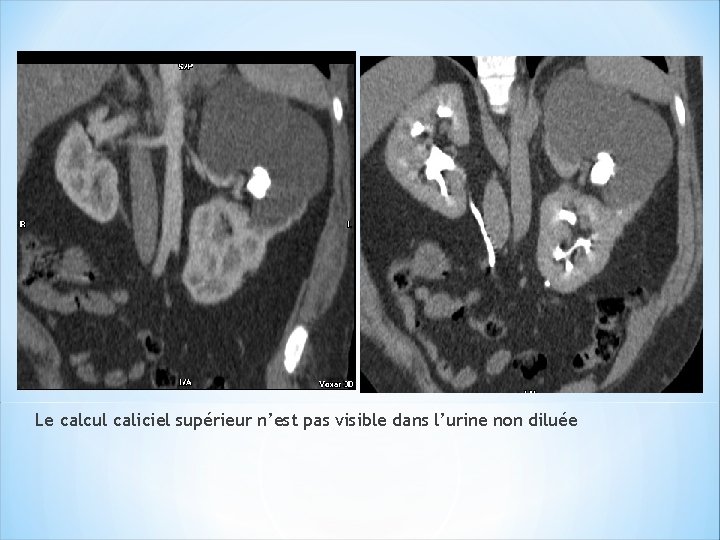

Intérêt de la dilution de l’urine: Urine non diluée a densité >>> celle de la plupart des calculs. >>> La plupart des calculs sont masqués. >>>>phase sans injection++ *Améliorer la visibilité des calculs sur la phase excrétoire: >>>>diluer les urines et distendre les cavités : ( densité< 500 UH). - absorption d’un litre d’eau – perfusion de 250 ml de sérum φ – furosémide : 10 mg IV

Le calcul caliciel supérieur n’est pas visible dans l’urine non diluée